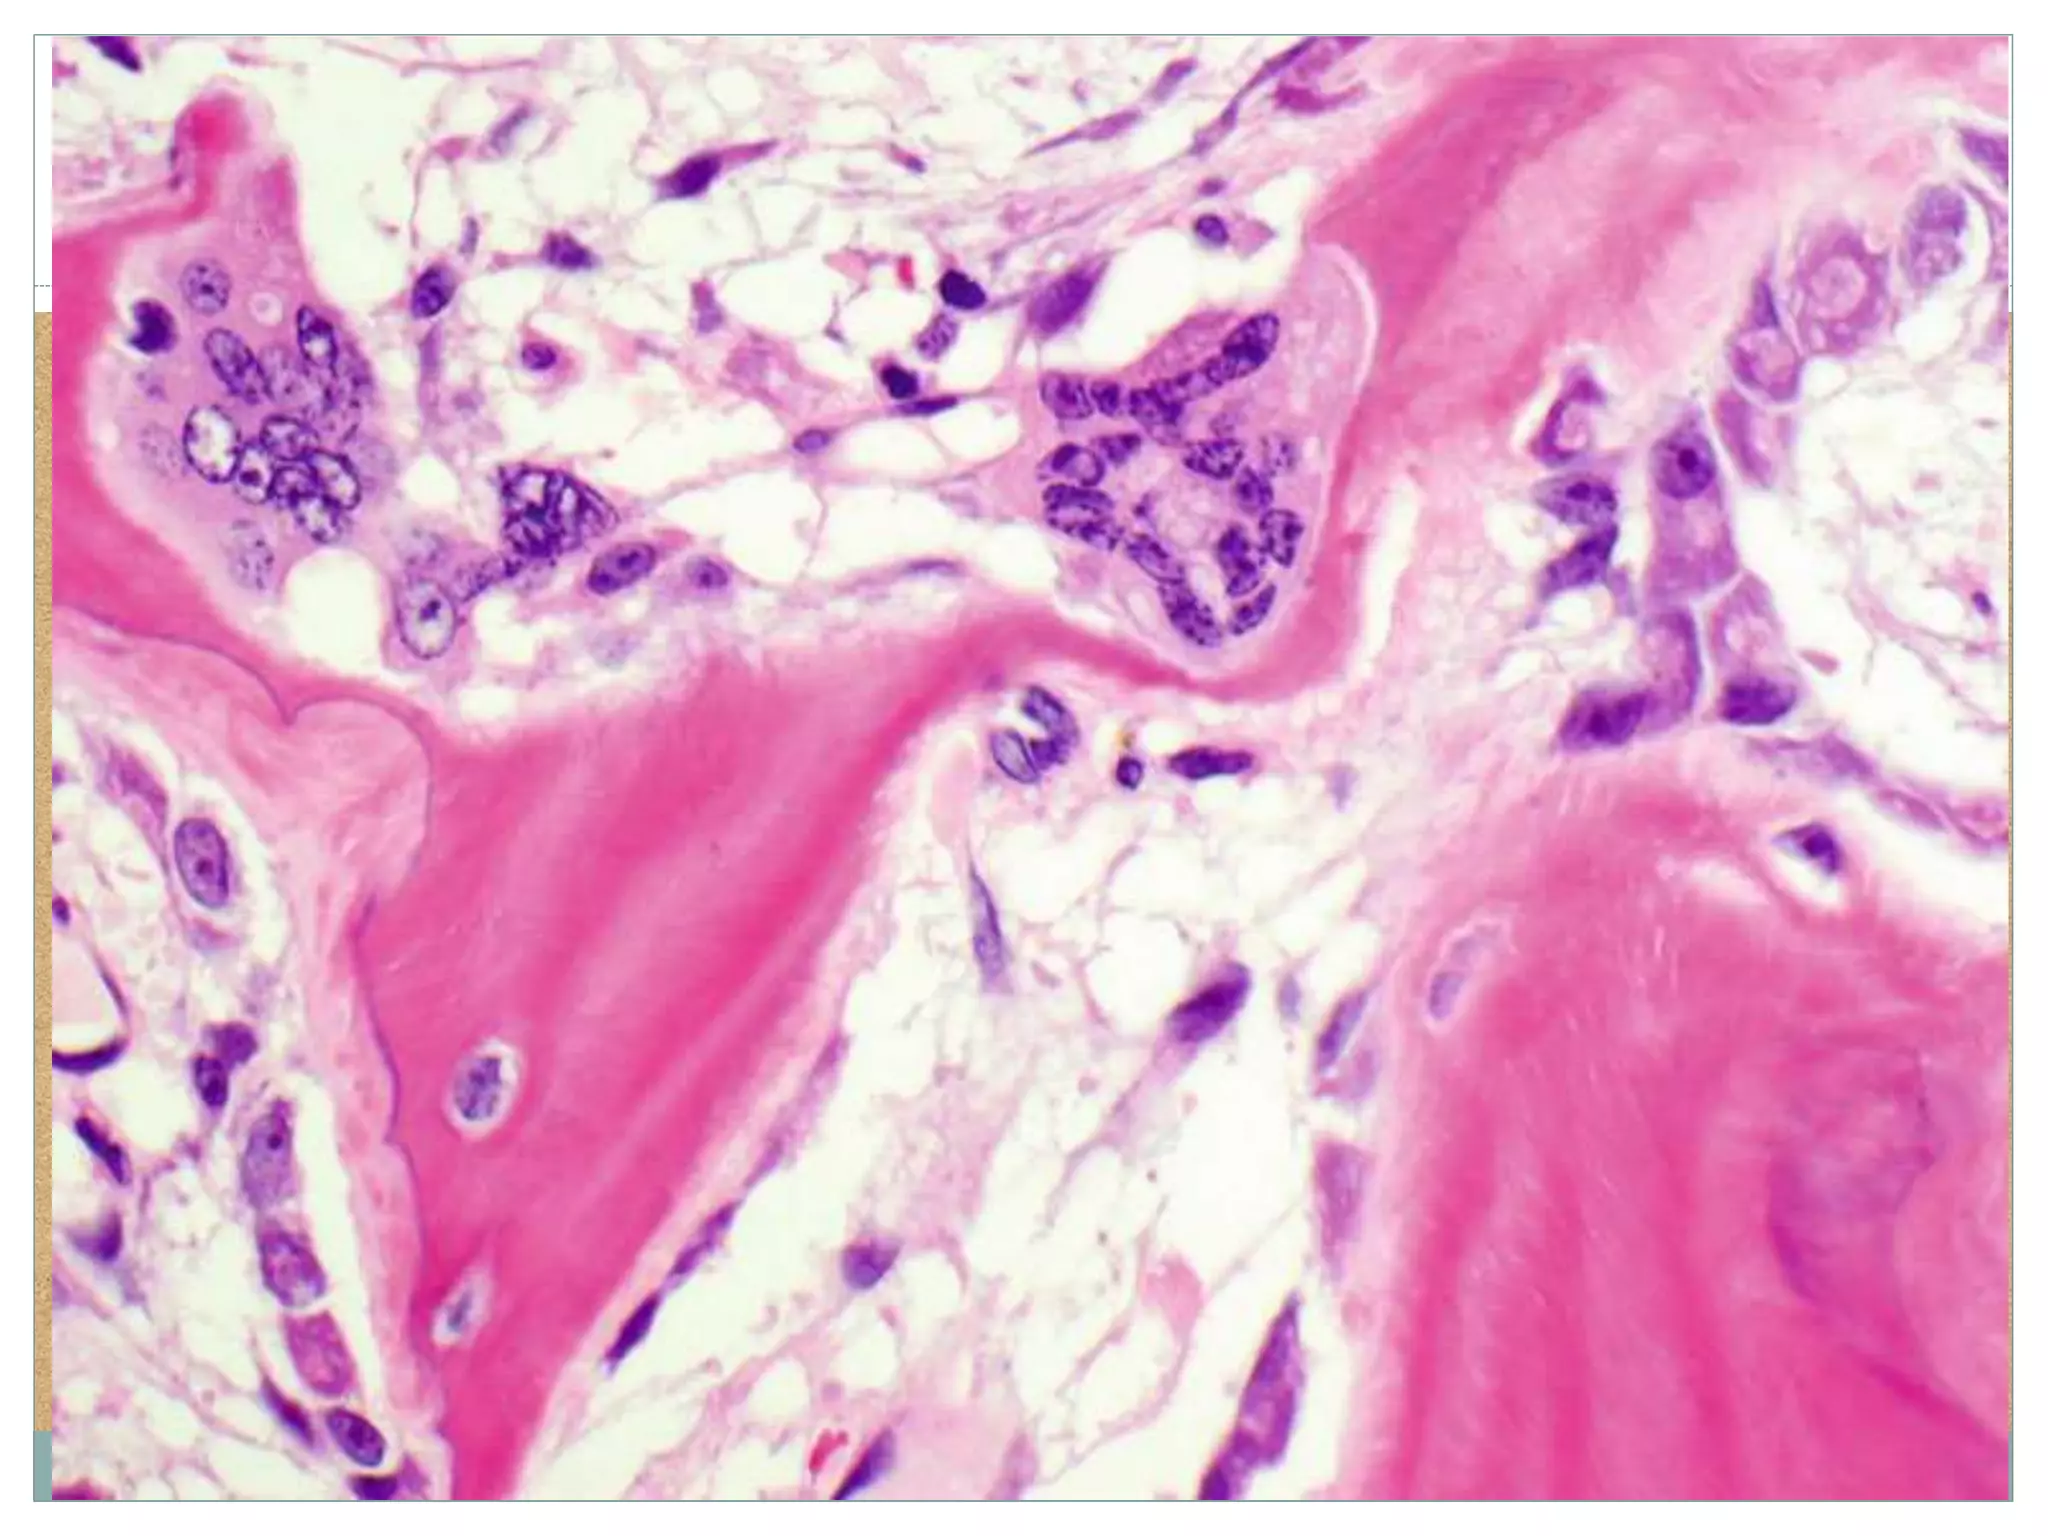

Woven Bone

Under conditions of rapid

turnover, e.g., normal

growth, fracture healing, or

under some pathologic

conditions as illustrated,

osteoid is deposited in

disorganized fashion

and is called woven bone

in contrast to lamellar

bone.

Lamellar bone

Bone Formation Woven Bone Underconditions of rapid turnover, e.g., normal growth, fracture healing, or under some pathologic conditions as illustrated, osteoid is deposited in disorganized fashion and is called woven bone in contrast to lamellar bone. Lamellar bone Woven bone